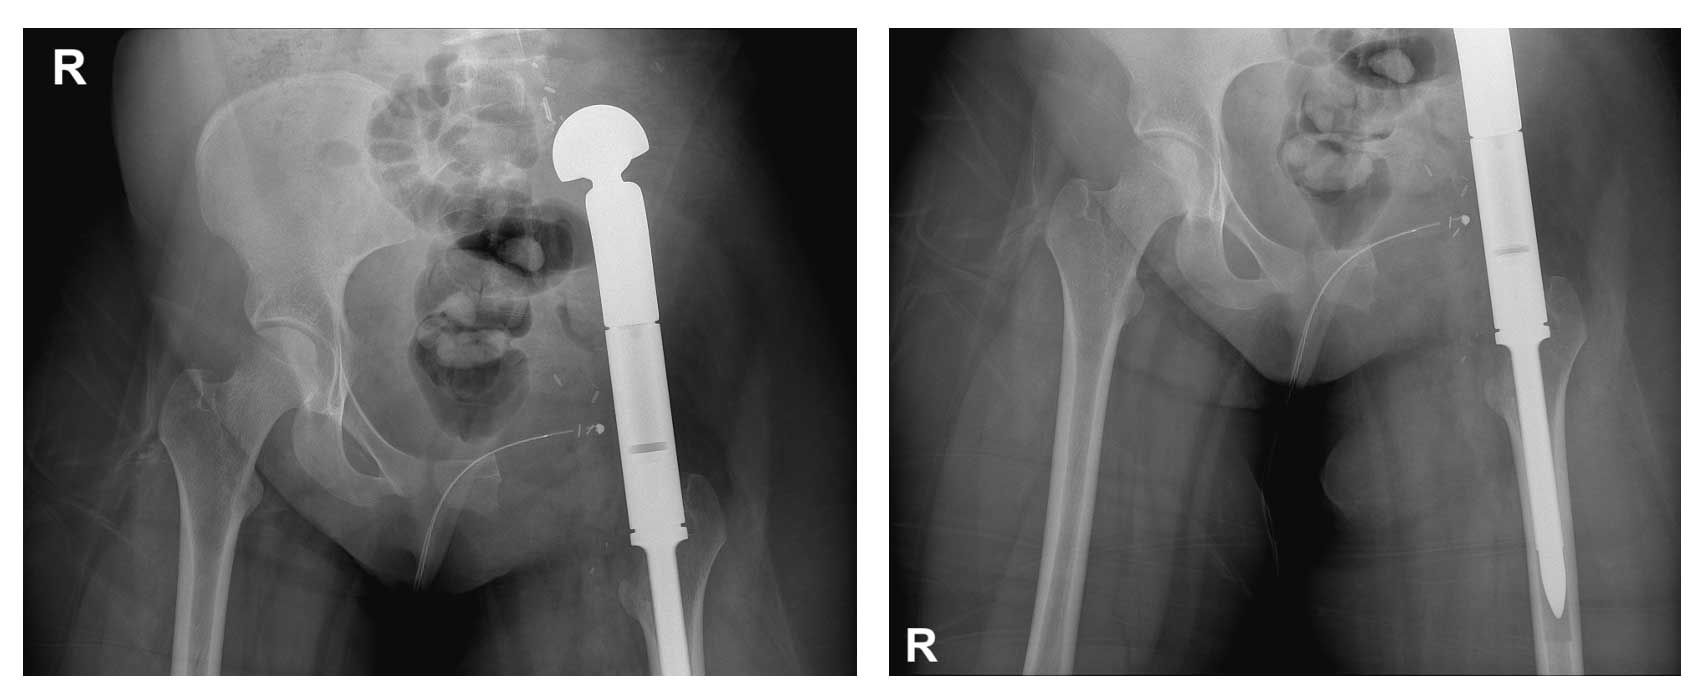

Ameliyat Sonrası: Röntgende hemipelvektomi sonrası tümör protezi ile uygulanan kalça transpozisyonu görülmekte.